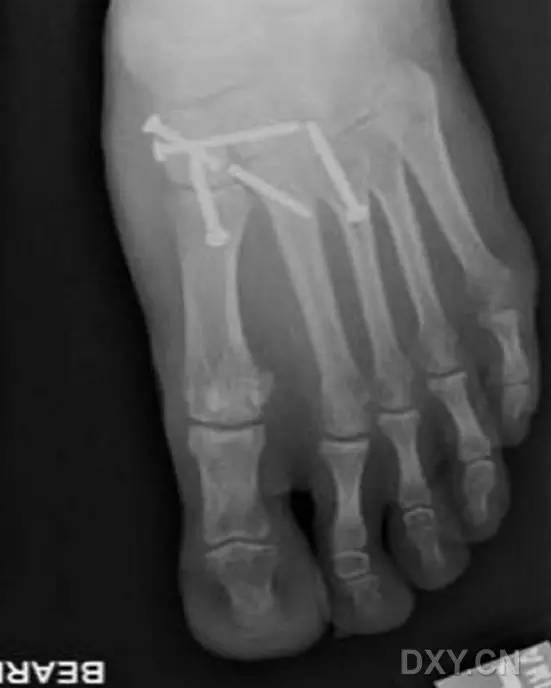

这一损伤的传统固定方式是将 1 枚螺钉(以下简称为 Lisfranc 螺钉)经内侧楔骨向第 2 跖骨基底置入(图 1)。

图 1. 传统的 Lisfranc 螺钉置入方法